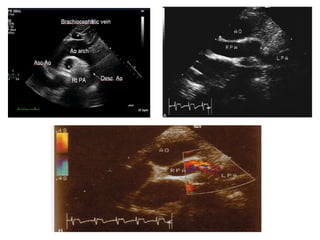

PAs

• The PAs are evaluated using a combination of 2D imaging and

color and spectral Doppler.

• The suprasternal and high left and right parasternal windows

are used to image the mediastinal PAs, although imaging may

be challenging in patients with larger body habitus.

• The main PA (MPA) is measured at its midpoint during systole.

• The subcostal long-axis, high left parasternal short-axis,

suprasternal short-axis, and right parasternal short-axis

views are helpful in visualizing the length of the RPA.

• The high left parasternal shortaxis and the suprasternal

long-axis (near parasagittal plane angled to the left) views

are useful in visualizing the length of the LPA.

• The distal LPA is more difficult to image than the RPA

because of interference from air in the lung and the left

bronchus.